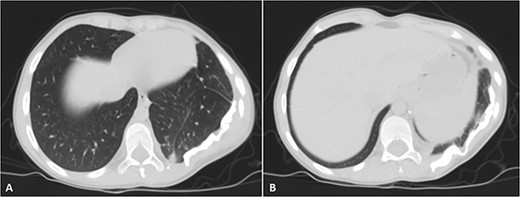

Selected coronal (A) and sagittal (B) cuts showing the size and the extension of the previously mentioned mass.